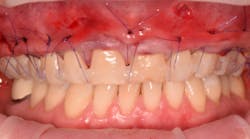

5. A full subperiosteal flap is then tunneled with appropriate instruments, and multiple A-PRF membranes are introduced inside the elevated tissue (figure 13). The gums are advanced toward the CEJ, and a tension-free flap release is performed and stabilized with sutures.

Coronally advanced flap (CAF) is maintained using an apical mattress suture (figure 14). Glycolon sutures 5.0 or 6.0 are the desired sutures to be able to maintain the flap in close contact with root proximity for at least three to four weeks.

This new biological approach involving blood derivatives A-PRF and I-PRF combined with precision minimally invasive surgery for root coverage demonstrates faster healing without the need of a donor site. The morbidity of GDT is decreased and patient case acceptance is higher compared with traditional grafts. Before-and-after pictures are shown below (figures 15–22).